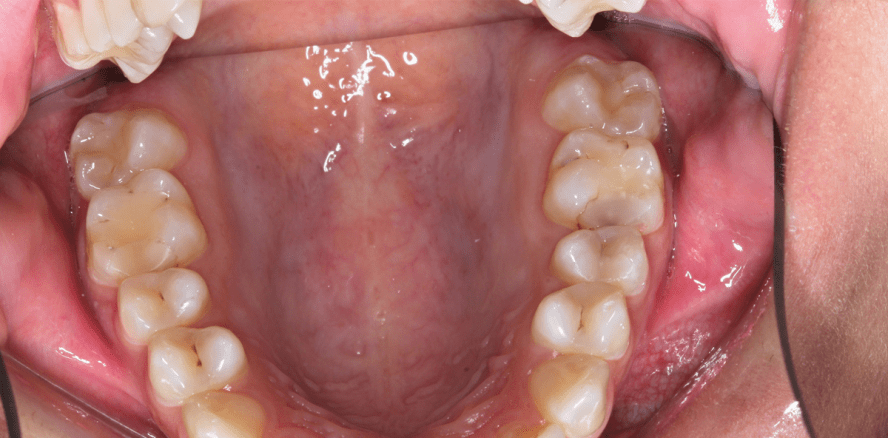

Erstmals ist nach den Regularien der AWMF (Arbeitsgemeinschaft der Wissenschaftlichen Medizinischen Fachgesellschaften) eine S1-Handlungsempfehlung zu Kompositrestaurationen im Seitenzahnbereich entstanden. Federführend durch die DGZ und die DGZMK wurden in Zusammenarbeit mit der DGR2Z wissenschaftliche Informationen zu Indikationen und Kontraindikationen direkter Kompositrestaurationen im Seitenzahnbereich unter Berücksichtigung unterschiedlicher Werkstoffgruppen sowie zu minimal-invasiv orientierten Vorgehensweisen zusammengetragen und informell konsentiert. Die Handlungsempfehlung finden Sie hier.